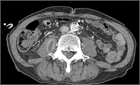

診断

1. 腰痛と発熱がみられる場合は、化膿性脊椎炎を想起する。腰痛は一般的な訴えであるが、発熱は腰痛のred flag sign(治療を要する重篤な原因を示唆する所見)の1つである。

1. 血行性の化膿性脊椎炎では血液培養で原因微生物が検出可能であるため、血液培養2セットの提出が必要である(推奨度1)